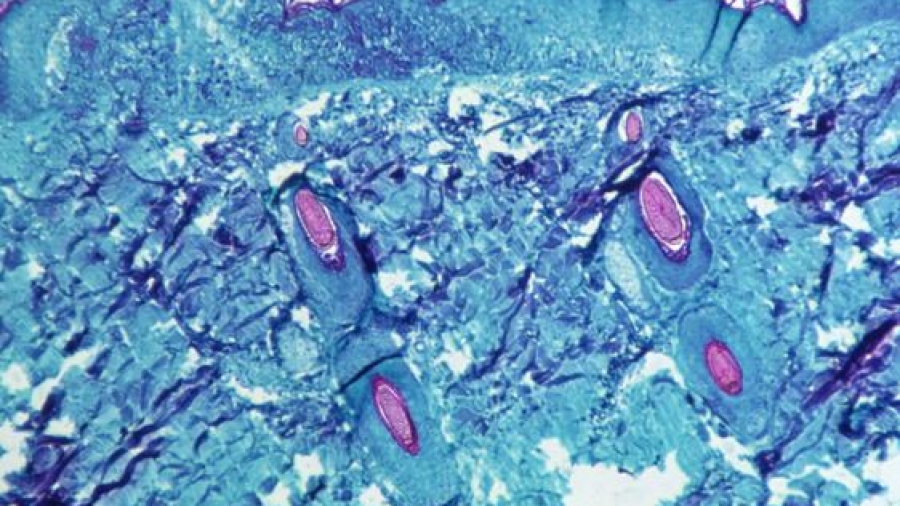

Η νόσος εκδηλώνεται με συμπτώματα, όπως πυρετό, κεφαλαλγία, μυαλγίες, λεμφαδενοπάθεια και εξάνθημα, το οποίο συνήθως ξεκινάει από την κεφαλή και επεκτείνεται στον κορμό, συμπεριλαμβάνοντας και παλάμες-πέλματα.

Αρχικά το εξάνθημα, που μερικές φορές συγχέεται με το εξάνθημα της ανεμοβλογιάς, εμφανίζεται με τη μορφή κηλίδων και βλατίδων, οι οποίες εξελίσσονται σε μικρές φυσαλίδες, φλύκταινες και κατόπιν σε εφελκίδες που τελικά υποχωρούν.

Η διάγνωση γίνεται με απομόνωση του ιού σε καλλιέργεια, ανίχνευση του DNA του ιού με PCR σε κλινικό δείγμα ή ανίχνευση παρουσίας orthopox-ιού σε ιστούς με ανοσοϊστοχημικές μεθόδους.